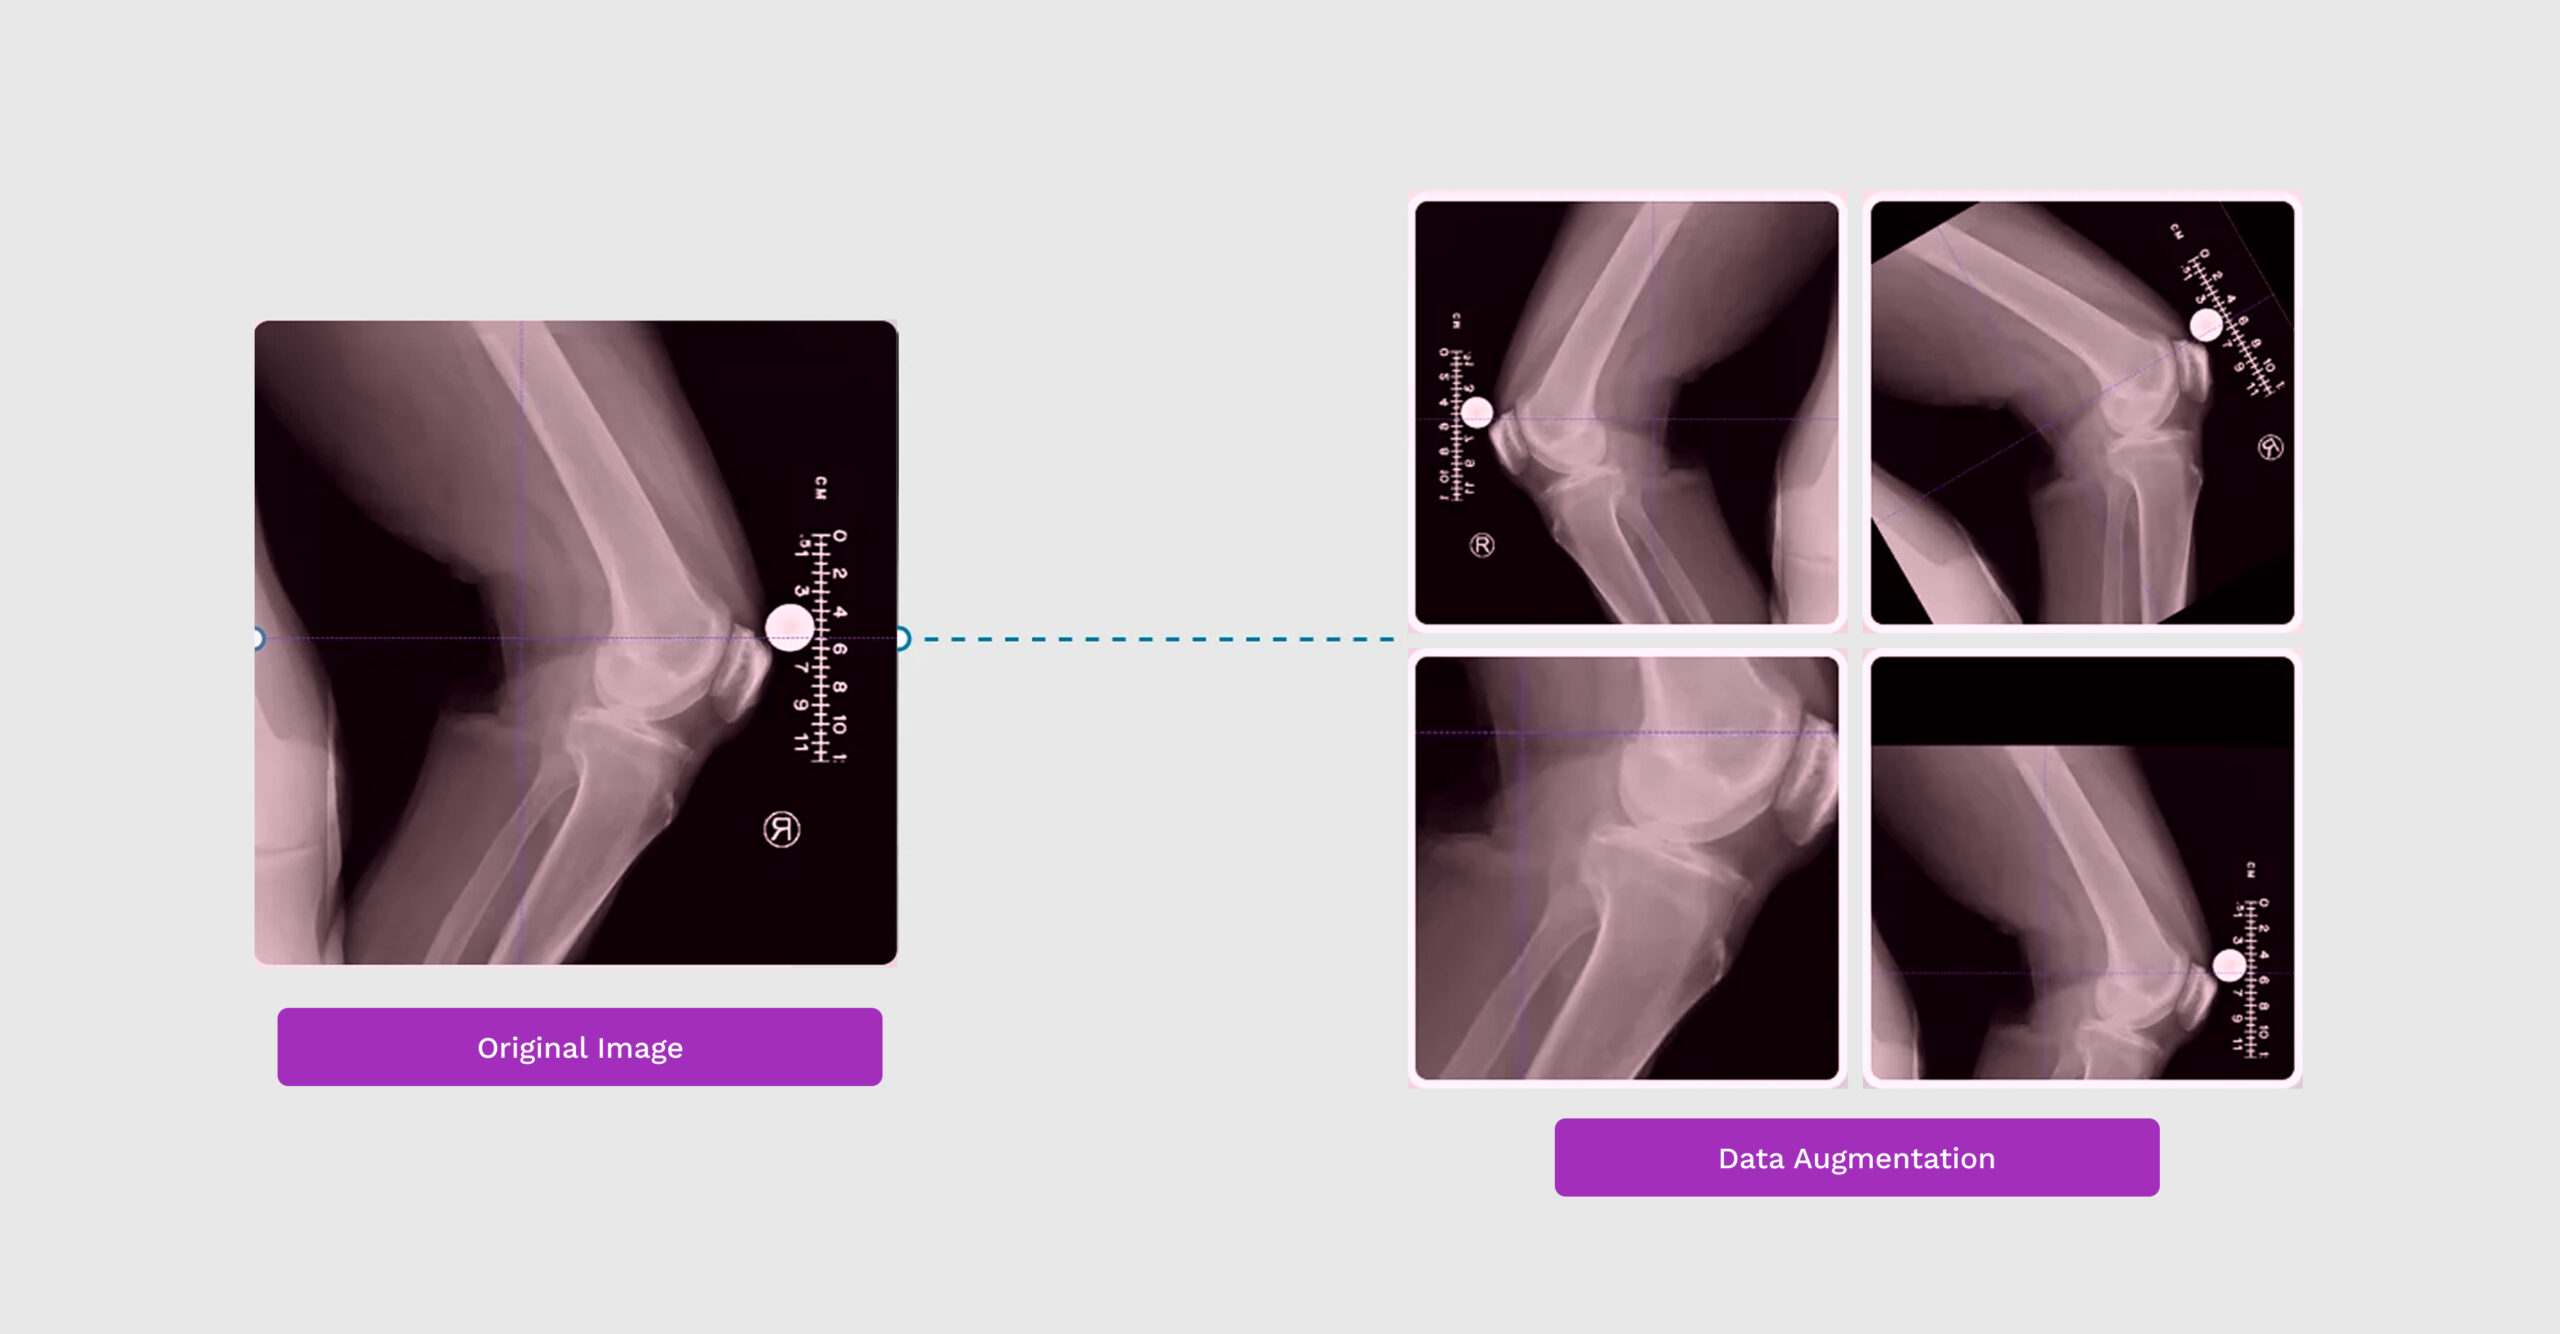

In deep learning, having a large, diverse dataset is crucial for training high-performing models. However, gathering extensive data can be costly and time-consuming. This is where data augmentation in deep learning comes in, offering a cost-effective way to expand and diversify training datasets. By applying a variety of transformations to the existing data, data augmentation […]